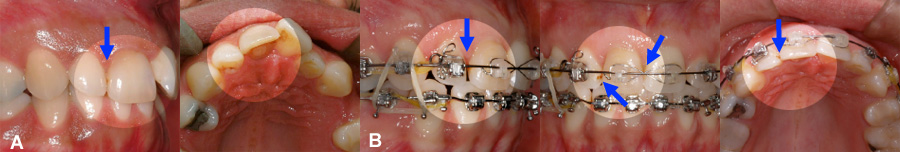

Apparition de caries entre des dents antérieures pendant l’orthodontie-2

(A) La rotation d’une centrale et latérale cache une carie sur la face interne de la latérale. (B) Après la correction des rotations, la carie est visible sur la latérale et peut être plus facilement accessible pour le dentiste afin d’être réparer.